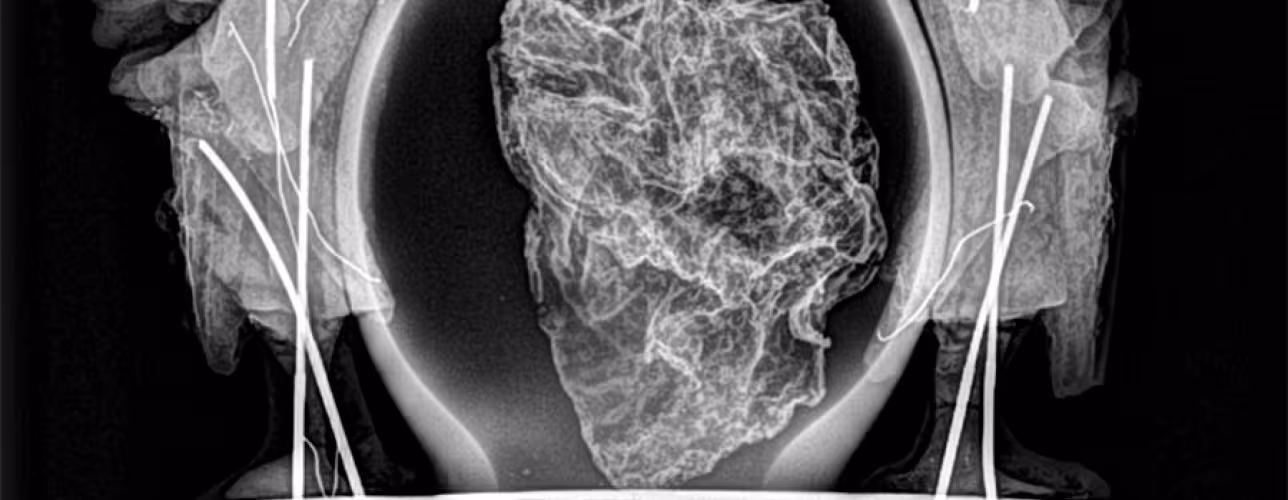

El Servicio de Patrimonio Histórico del Ejecutivo foral ha realizado diversas intervenciones en el corazón de Carlos II de Navarra destinadas a retornar a su lugar los objetos en las mejores condiciones de conservación, aplicar tratamientos de estabilización que garanticen su preservación óptima, y obtener datos para iniciar un proyecto de investigación del conjunto funerario.

En concreto, se han tomado muestras microscópicas de los restos de todos los componentes de las piezas, tejidos, ceras, policromías, madera, así como de los restos biológicos, pólenes, fibras o colonias de hongos incluidas, y del propio corazón para hacer el estudio de ADN y antropológico forense.

Todos los componentes y datos, acompañados de material gráfico, se han puesto en manos de diversas disciplinas para que, cuando las circunstancias lo permitan, se puedan elaborar estudios que ayuden a conocer mejor el proceso de embalsamado, la confección de los recipientes de custodia, las distintas intervenciones que ha sufrido el corazón desde su sepultura inicial el 18 de enero de 1387 hasta la actualidad, y todo aquello que la ciencia permita extraer y aportar al conocimiento del corazón del rey.

También han tomado parte el Departamento de Biología de la Universidad de Navarra que tomó las muestras biológicas; el gabinete ‘Medicis’ que realizó un TAC; Alex Duró que realizó la fotogrametría; la empresa ‘Muraria’ por la revisión documental y la gestión del diseño expositivo; y la empresa Moreno Valles que trasladó la pieza.